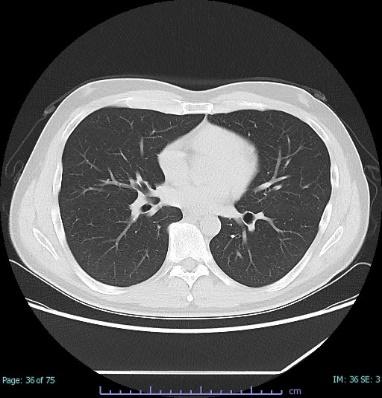

病院でレントゲン写真やCTを撮ってもらうのは「外部被ばく」です。

医療の分野では、放射線を使用した検査として、レントゲン検査・胃バリウム検査・CT検査・マンモグラフィ検査などがあります。